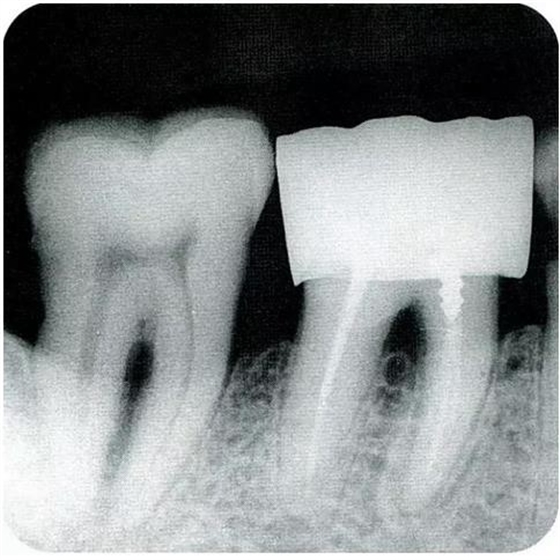

▼圖6-1下頜第一后磨牙的頰舌間存在III度的根分叉病變,預(yù)在進(jìn)行牙根分割后保留遠(yuǎn)中根。

▼圖6-2中下頜第一后磨牙雖然切除了一半,但是遠(yuǎn)中根也有2根分根,所以不得已拔除(被拔除遠(yuǎn)中根的近中面觀察)。